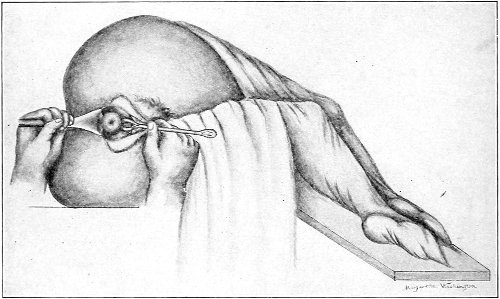

Fig. 11.—The cervix uteri exposed with the Sims speculum.

Fig. 12.—The knee-chest position.

The genu-pectoral position or the knee-chest position is shown in Fig. 12. The side of the face is upon the pillow; the breast is upon the table; the thighs are vertical. In 33 this position the intestines fall from the pelvis, and the other pelvic viscera are drawn upward by the force of gravity. If the anus is opened, air rushes in and distends the rectum. If the perineum is retracted, air enters and distends the vagina. If the urethra is opened, the bladder is likewise distended. The position is the most useful one for inspection of the rectum, vagina and vaginal cervix, and the bladder.

The Sims speculum, with the woman in the dorsal, the Sims, or the knee-chest position, is the most useful instrument by which to expose the cervix uteri for any of the minor operations of gynecology. The manipulations of the operator are not hampered by working between metal walls.

Examination of the Rectum.—If the woman is placed in the knee-chest position, a most satisfactory inspection of the whole of the rectum may be made. The woman should be placed in this position with the buttocks before a good light, and the posterior margin of the anus should be retracted by the small blade of a Sims speculum; the rectum will immediately become distended with air and the rectal walls will be well exposed. Or the rectal specula (Figs. 13, 14) may be used. In employing the longer of these instruments it is best to use light reflected from a head-mirror or thrown directly from an electric head-light into the speculum.